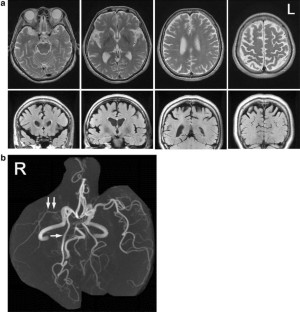

A 65-year-old woman developed progressive apraxic agraphia, characterized by poorly formed graphemes, a kanji (Japanese morphograms) recall impairment, relatively preserved oral spelling of kanji characters, and incorrect stroke sequences on writing accompanied by micrographia over a 3-year period. She also showed minor degrees of rigidity, limb-kinetic apraxia, and ideomotor apraxia of the left hand. Although asymmetric rigidity and limb-kinetic apraxia strongly suggested corticobasal degeneration, 11C-Pittsburgh compound B positron emission tomography (PiB-PET) showed the predominantly right-sided accumulation of amyloid β in the cortices and striatum. 18F-fluoro-deoxy-glucose PET and single photon emission computed tomography with a 99mTc-ethylcysteinate dimer (ECD-SPECT) also revealed predominantly right-sided hypometabolism and hypoperfusion in the primary sensorimotor cortex, posterior cingulate gyrus, temporoparietal cortices, frontal cortices, thalamus, and basal ganglia, a pattern characteristic of both corticobasal degeneration and Alzheimer’s disease. The findings suggest that progressive apraxic agraphia with micrographia presenting as corticobasal syndrome can show an Alzheimer’s disease pathology. It is also suggested that ideomotor apraxia of the left hand can occur without a callosal lesion, and is caused by hypometabolism or hypoperfusion in the right frontal and parietal cortices, as revealed by PET and SPECT.

Fig. 1